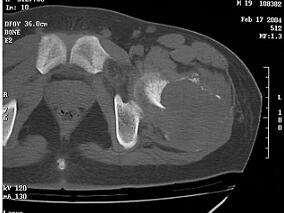

1小时条评论40岁女性确诊肾上腺原发性醛固酮增多症,术前准备和手术具体步骤,详见以下手术图谱 一、病例资料 女性,40岁,头晕、手足麻木6个月,CT检查发现左肾上腺直径1.8cm占位病变(图5-2-1),体检血压185/100mmHg,血钾2.3mmol/ml,术前诊断肾上腺原发性醛固酮增多症。 ...